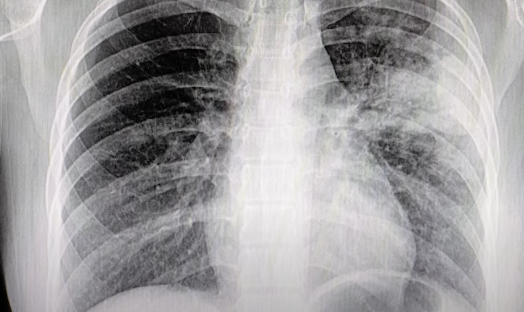

폐렴의 진단과 치료 방법 🏥

폐렴은 증상만으로는 감기나 기관지염과 구분이 어려워, 병원에서 정확한 검사가 필요합니다.

진단 방법

- 흉부 엑스레이